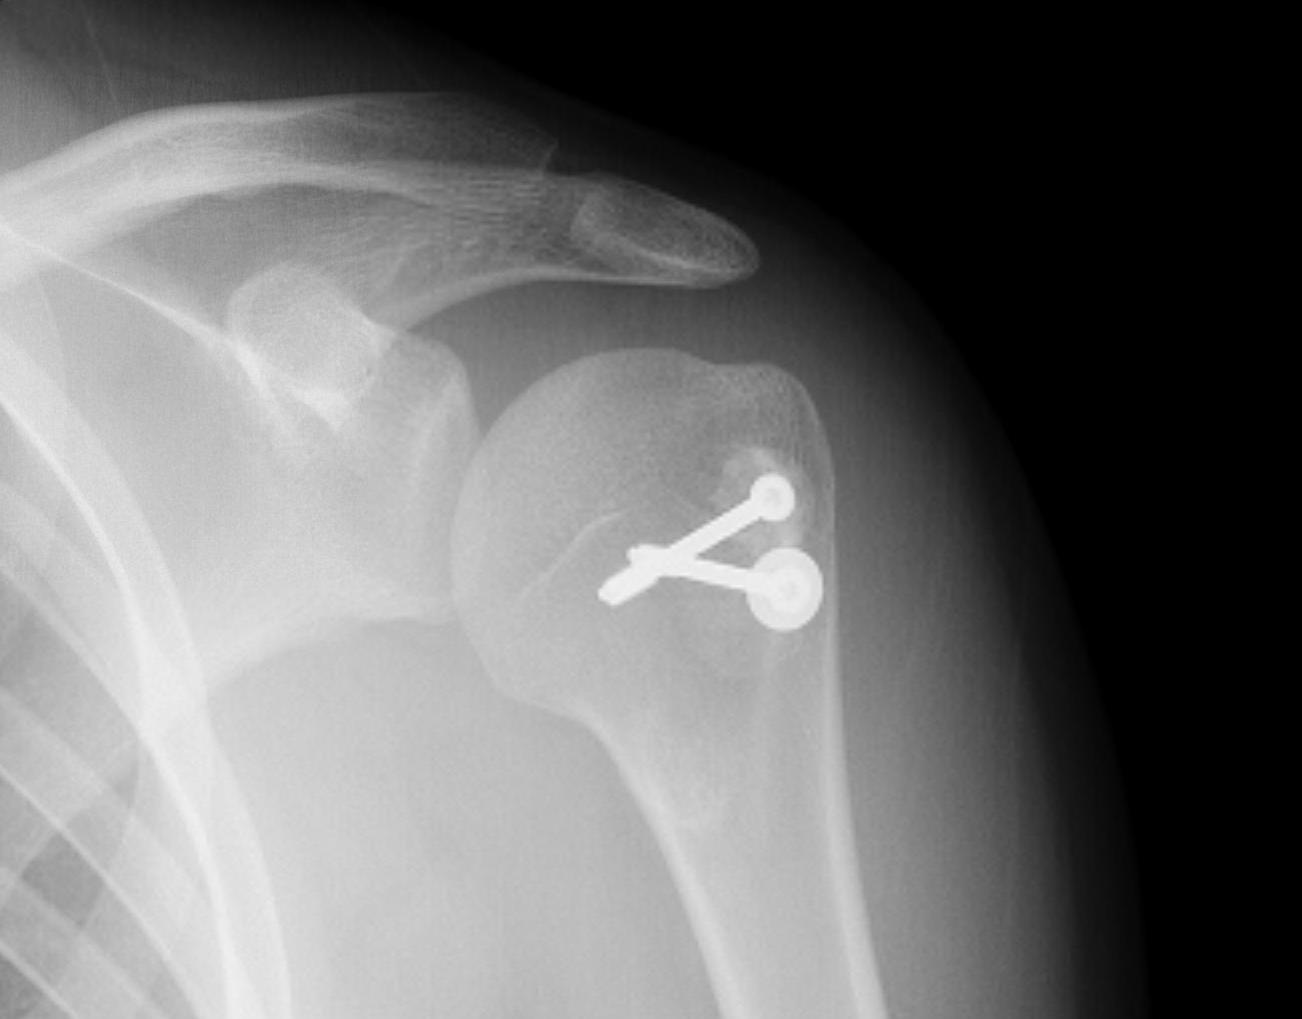

proximal humerus fracture Background ORIF with locking plate Arthroplasty Greater tuberosity fractures Lesser tuberosity fractures / avulsions Book traversal links for Proximal humerus fractures ‹ Pectoralis Major Tears Up Background ›